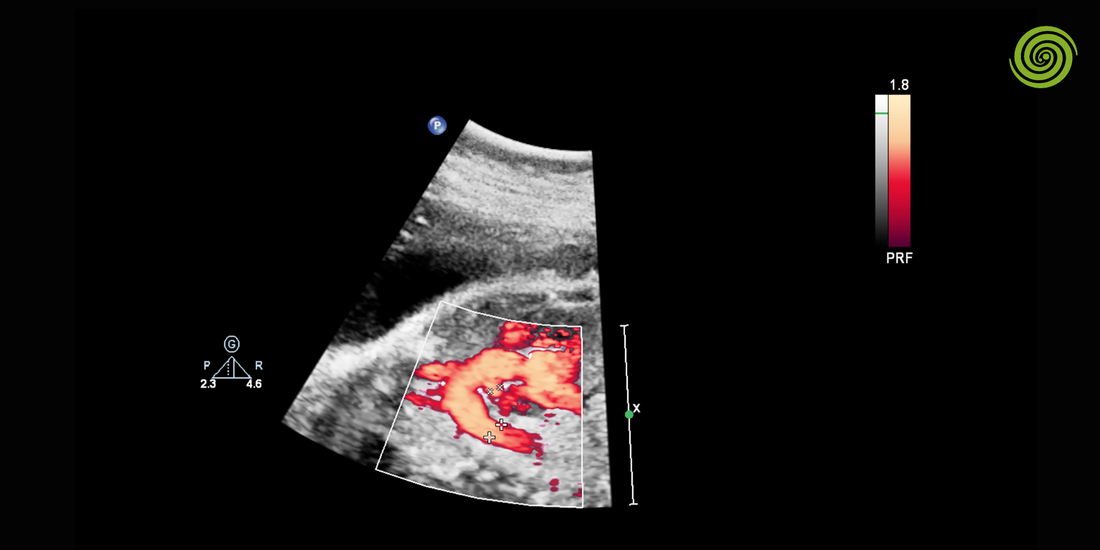

Monitoreos hemodinámicos mediante ultrasonido

Uno de los mayores aportes de la ecografía en insuficiencia cardíaca es su capacidad de monitoreo continuo.

Los monitoreos hemodinámicos incluyen:

-

Variación de diámetro de vena cava.

Evaluación seriada de fracción de eyección.

Seguimiento de respuesta a diuréticos.

Evaluación de congestión pulmonar mediante líneas B.

A diferencia de estudios estáticos, el ultrasonido permite observar cambios dinámicos en tiempo real.

Esto resulta clave en pacientes hospitalizados o en unidades de cuidado intensivo.